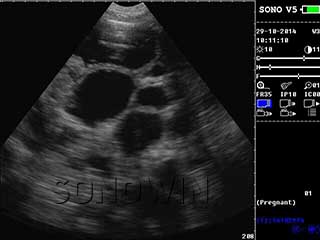

优质图像